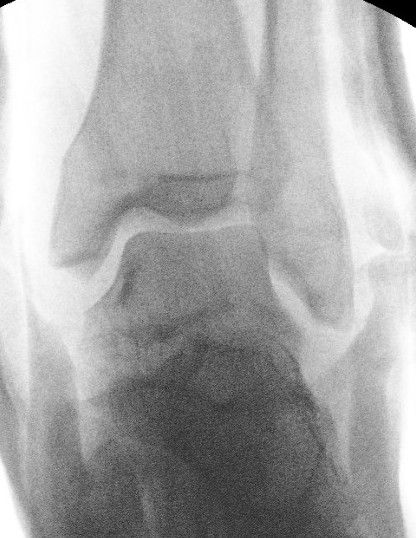

Xray / CT

Ensure no displacement / malalignment

Canale view

- evaluates talar neck

- foot everted 15 deg

- look for medial shortening / varus

Xrays

| AP | Lateral | Canale View |

|---|---|---|

| Entry point of the screws |

Evaluate neck reduction

|

Evaluates the neck reduction |

Lateral off articular surface Medial through articular cartilage |

Depth of screws |

Beam angled 75o to foot Foot 15o pronated |